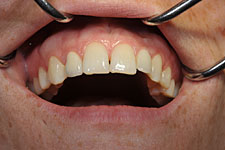

Im Vergleich zu Kronen auf natürlichen Zähnen sind Implantatkronen meist schöner, da natürliche Zähne durch den Zahnnerv oder eine ungünstige Position die Möglichkeiten von Zahnarzt und Zahntechniker einengen. Außerdem ist der natürliche Rückzug des Zahnfleisches an Implantaten deutlich geringer als an den eigenen Zähnen - im sichtbaren Bereich ein deutlicher Vorteil.